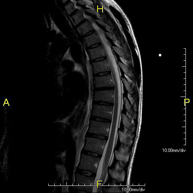

- Thoracic spine MRI

This non-invasive diagnostic procedure uses an electromagnetic field and radio waves (from a transmitter and receiver) to acquire high-definition anatomical images of the thoracic spine. It is a radiation-free procedure. Indicated for: trauma, degenerative problems, hernias, tumours.